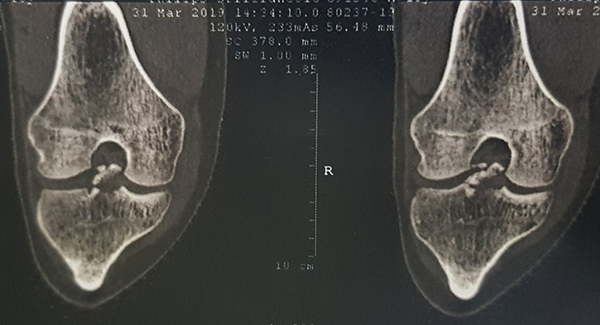

Se solicitó Rx, donde se constató fractura de espina tibial grado 3 (fig. 1), además, una tomografía axial computada (fig. 2), aportando un patrón conminuto del fragmento y RM, donde se evidenció, además de la fractura de espina tibial, una lesión en asa de balde del menisco interno (fig. 3).

Figura 2: Tomografía axial computada de rodilla derecha. Imágenes coronales que muestran la fractura de espina tibial.